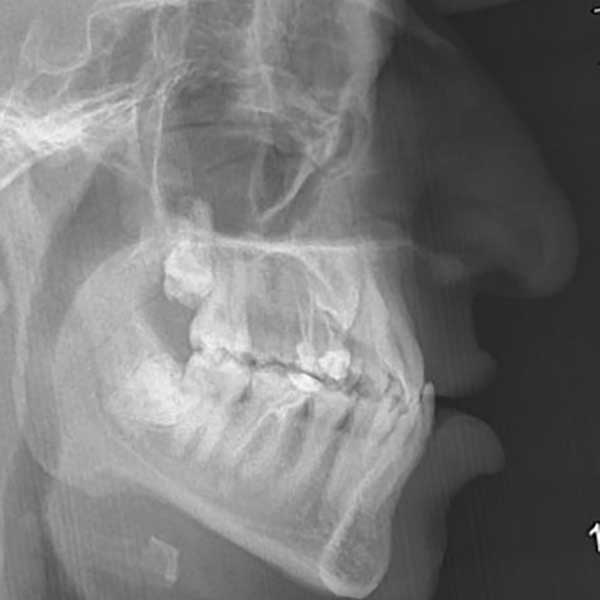

“راجعتني هذه الشابة قبل عدة سنوات وهي تعاني من ازدحام شديد في أسنانها، لدرجة أن أحد أنيابها قد بزغ بشكل مرتفع وبعيد عن مكانه الطبيعي. طلبت مني صديقتنا مساعدتها وترتيب أسنانها ولكن من دون قلع أسنان.

ولحسن الحظ في حالتها كان بالإمكان اجراء المعالجة من دون قلع أسنان، وقد اخترت استخدام التقويم ذاتي الربط (تقويم الدايمون) لأنه يساعد في تحريك الأسنان وتوسيع الفكين. وبالفعل، في نهاية العلاج نجحنا في رصف الأسنان بشكل ممتاز، وبات بإمكان مراجعتنا الابتسام بثقة وسعادة مجدداً.